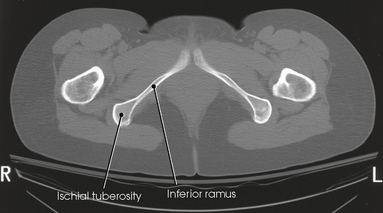

The femur is the longest, strongest, and heaviest bone in the body. The proximal end of the femur consists of a head, a neck, and two large processes: the greater and lesser trochanters (Fig. 7-4). The smooth, rounded head is connected to the femoral body by a pyramid-shaped neck and is received into the acetabular cavity of the hip bone. A small depression at the center of the head, the fovea capitis, attaches to the ligamentum capitis femoris (Fig. 7-5; see Fig. 7-4). The neck is constricted near the head but expands to a broad base at the body of the bone. The neck projects medially, superiorly, and anteriorly from the body. The trochanters are situated at the junction of the body and the base of the neck. The greater trochanter is at the superolateral part of the femoral body, and the lesser trochanter is at the posteromedial part. The prominent ridge extending between the trochanters at the base of the neck on the posterior surface of the body is called the intertrochanteric crest. The less prominent ridge connecting the trochanters anteriorly is called the intertrochanteric line. The femoral neck and the intertrochanteric crest are two common sites of fractures in elderly adults. The superior portion of the greater trochanter projects above the neck and curves slightly posteriorly and medially.

Fig. 7-4 Proximal right femur. A, Anterior aspect. B, Medial aspect. The body is positioned 15 to 20 degrees posterior from head. C, Posterior aspect. D, Posterior aspect of right proximal human femur. Note anatomic details and compare with C.